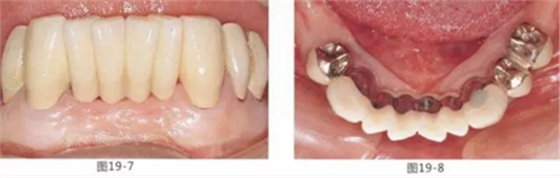

有少數(shù)牙體殘存的病例,需要進行修復(fù)處理,將基牙和鉤牙部位的牙周袋去除以及對頰舌側(cè)進行FGG(游離齦移植)來獲取附著齦的病例

圖19-7 佩戴最終修復(fù)5年后的唇頰側(cè)面照。

圖19-8 同時期下側(cè)咬合面照。